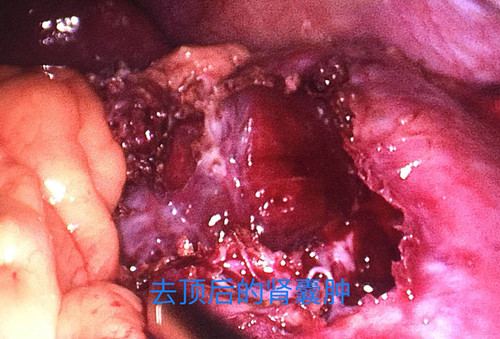

泌尿外科手术效果图